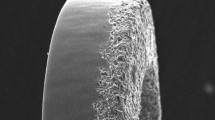

Coating characteristics

The stent and tube surfaces were investigated in a scanning electron microscope (SEM) prior to and after the in vivo and in vitro experiment. The coating was not notably affected by either experimental setup (Fig. 5a,b). The contact angle was measured for three liquids: whole blood, blood plasma, and deionized water (DIW). Increased contact angles in the coated group were observed across all measurements (Fig. 5c–h).

SEM images of the coated surface prior to implantation (a) and after implantation (b). Camera images of individual contact angle measurements of whole blood, blood plasma and DI water (c–e) and statistical analysis of the measurements (f–h). Significant differences are observed across all measurements.

Nanostructuring of materials is a common way of achieving superhydrophobic surfaces36. Although the investigated coatings do not exhibit such a feature, they show a significant increase in contact angles with DIW, blood plasma, and whole blood (Fig. 5c–h), which could partly explain the decreased protein adsorption. For example, nanostructured titanium has been shown to reduce the immune response, specifically monocyte adhesion, although in vitro37. Hydrophobic surfaces have also been shown to increase the flow shear rate at the surface, facilitating easier protein removal after eventual buildup38. These effects in combination could explain the reduced levels of TAT and other biomarkers in the coated group compared to controls in the in vitro experiments for both porcine and human blood39,40,41. The present findings corroborate previous studies showing that the absorption of fibrinogen on noble metals is reduced14. As mentioned above, this reduction is believed to be directly related to the degree of nanotopography that the metal composition shows in the SEM analyses42. In contrast to this, hydrophilic surface properties have been demonstrated to facilitate endothelialization43. Arguably, an equally important property is to inhibit protein adhesion that both improves endothelialization and reduces the subsequent thrombus formation cascade reaction44. Although the coating in the present study is not hydrophilic it is believed to provide an increased hemocompatibility due to the reduced protein adhesion.